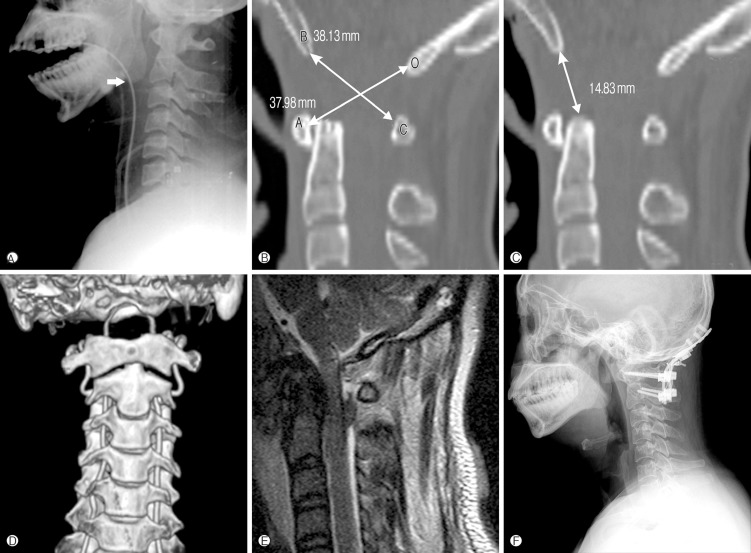

Xray / CT measurements

Frequently missed on xray

Basion-Dens Interval / BDI

- basion to tip of dens

- vertical displacement > 12 mm

Basion-Axial Interval / BAI

- basion to posterior border ondontoid

- anterior displacement > 4 mm

Power Ratio BC/AO > 1

- basion to posterior arch / opisthion to anterior arch

From: Kim et al Korean Journal of Spine 2012